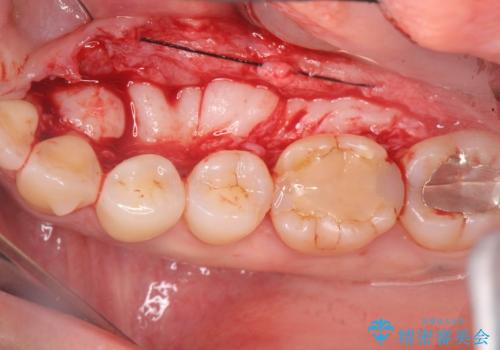

話すのに邪魔な、下顎骨隆起の切除

- 矯正治療を開始するのに伴い、滑舌を含めた改善を計るために、発音の邪魔となる下顎骨隆起の切除を計画します。

手術時間は約30分程度(大きさにより)今回は手術中に、静脈麻酔を行うことで負担なく治療を行う計画としました。

長年気になっていた骨隆起が短時間でなくなり、満足いただくことができました。